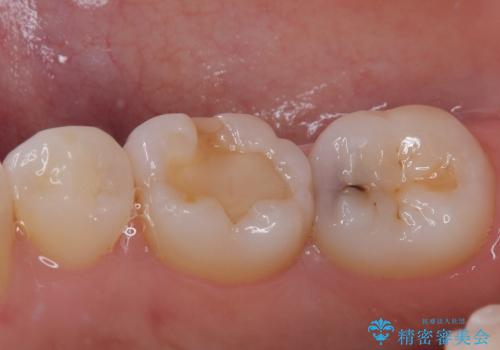

- 右下が黒くなってるとのことで来院された患者様です。レントゲン撮影により虫歯を認め、神経の反応の試験を行い正常な結果を得られたので、セラミックインレーによる修復治療を行っていくことにしました。

拡大鏡視野下で虫歯の除去を行い、セラミックインレーに適した形に整えました。